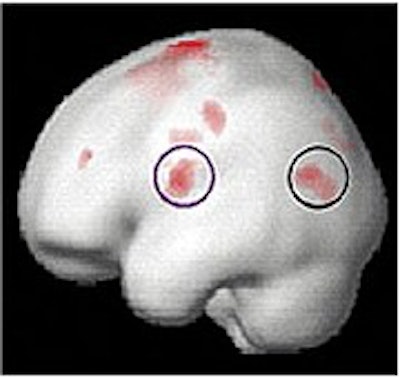

At the beginning of the study, MRI scans of the 20 dyslexic subjects contrasted sharply with those of the 12 normal readers in the control group; the dyslexic subjects' scans showed a lack of activity in the language-critical temporal regions of the brain.

Brain function in child with no reading disability (top); brain function in child with developmental dyslexia (middle); children with dyslexia show increased brain function after training (below). Images courtesy of Elise Temple, Ph.D.

At the end of the eighth week, the investigators found that, among the dyslectic subjects, areas of the brain critical to reading skills had become activated, and had begun to function more normally. Other regions of the brain also showed activity on the MRI scans, suggesting a gradual compensatory process that would help the dyslexic subjects learn to read more fluently.